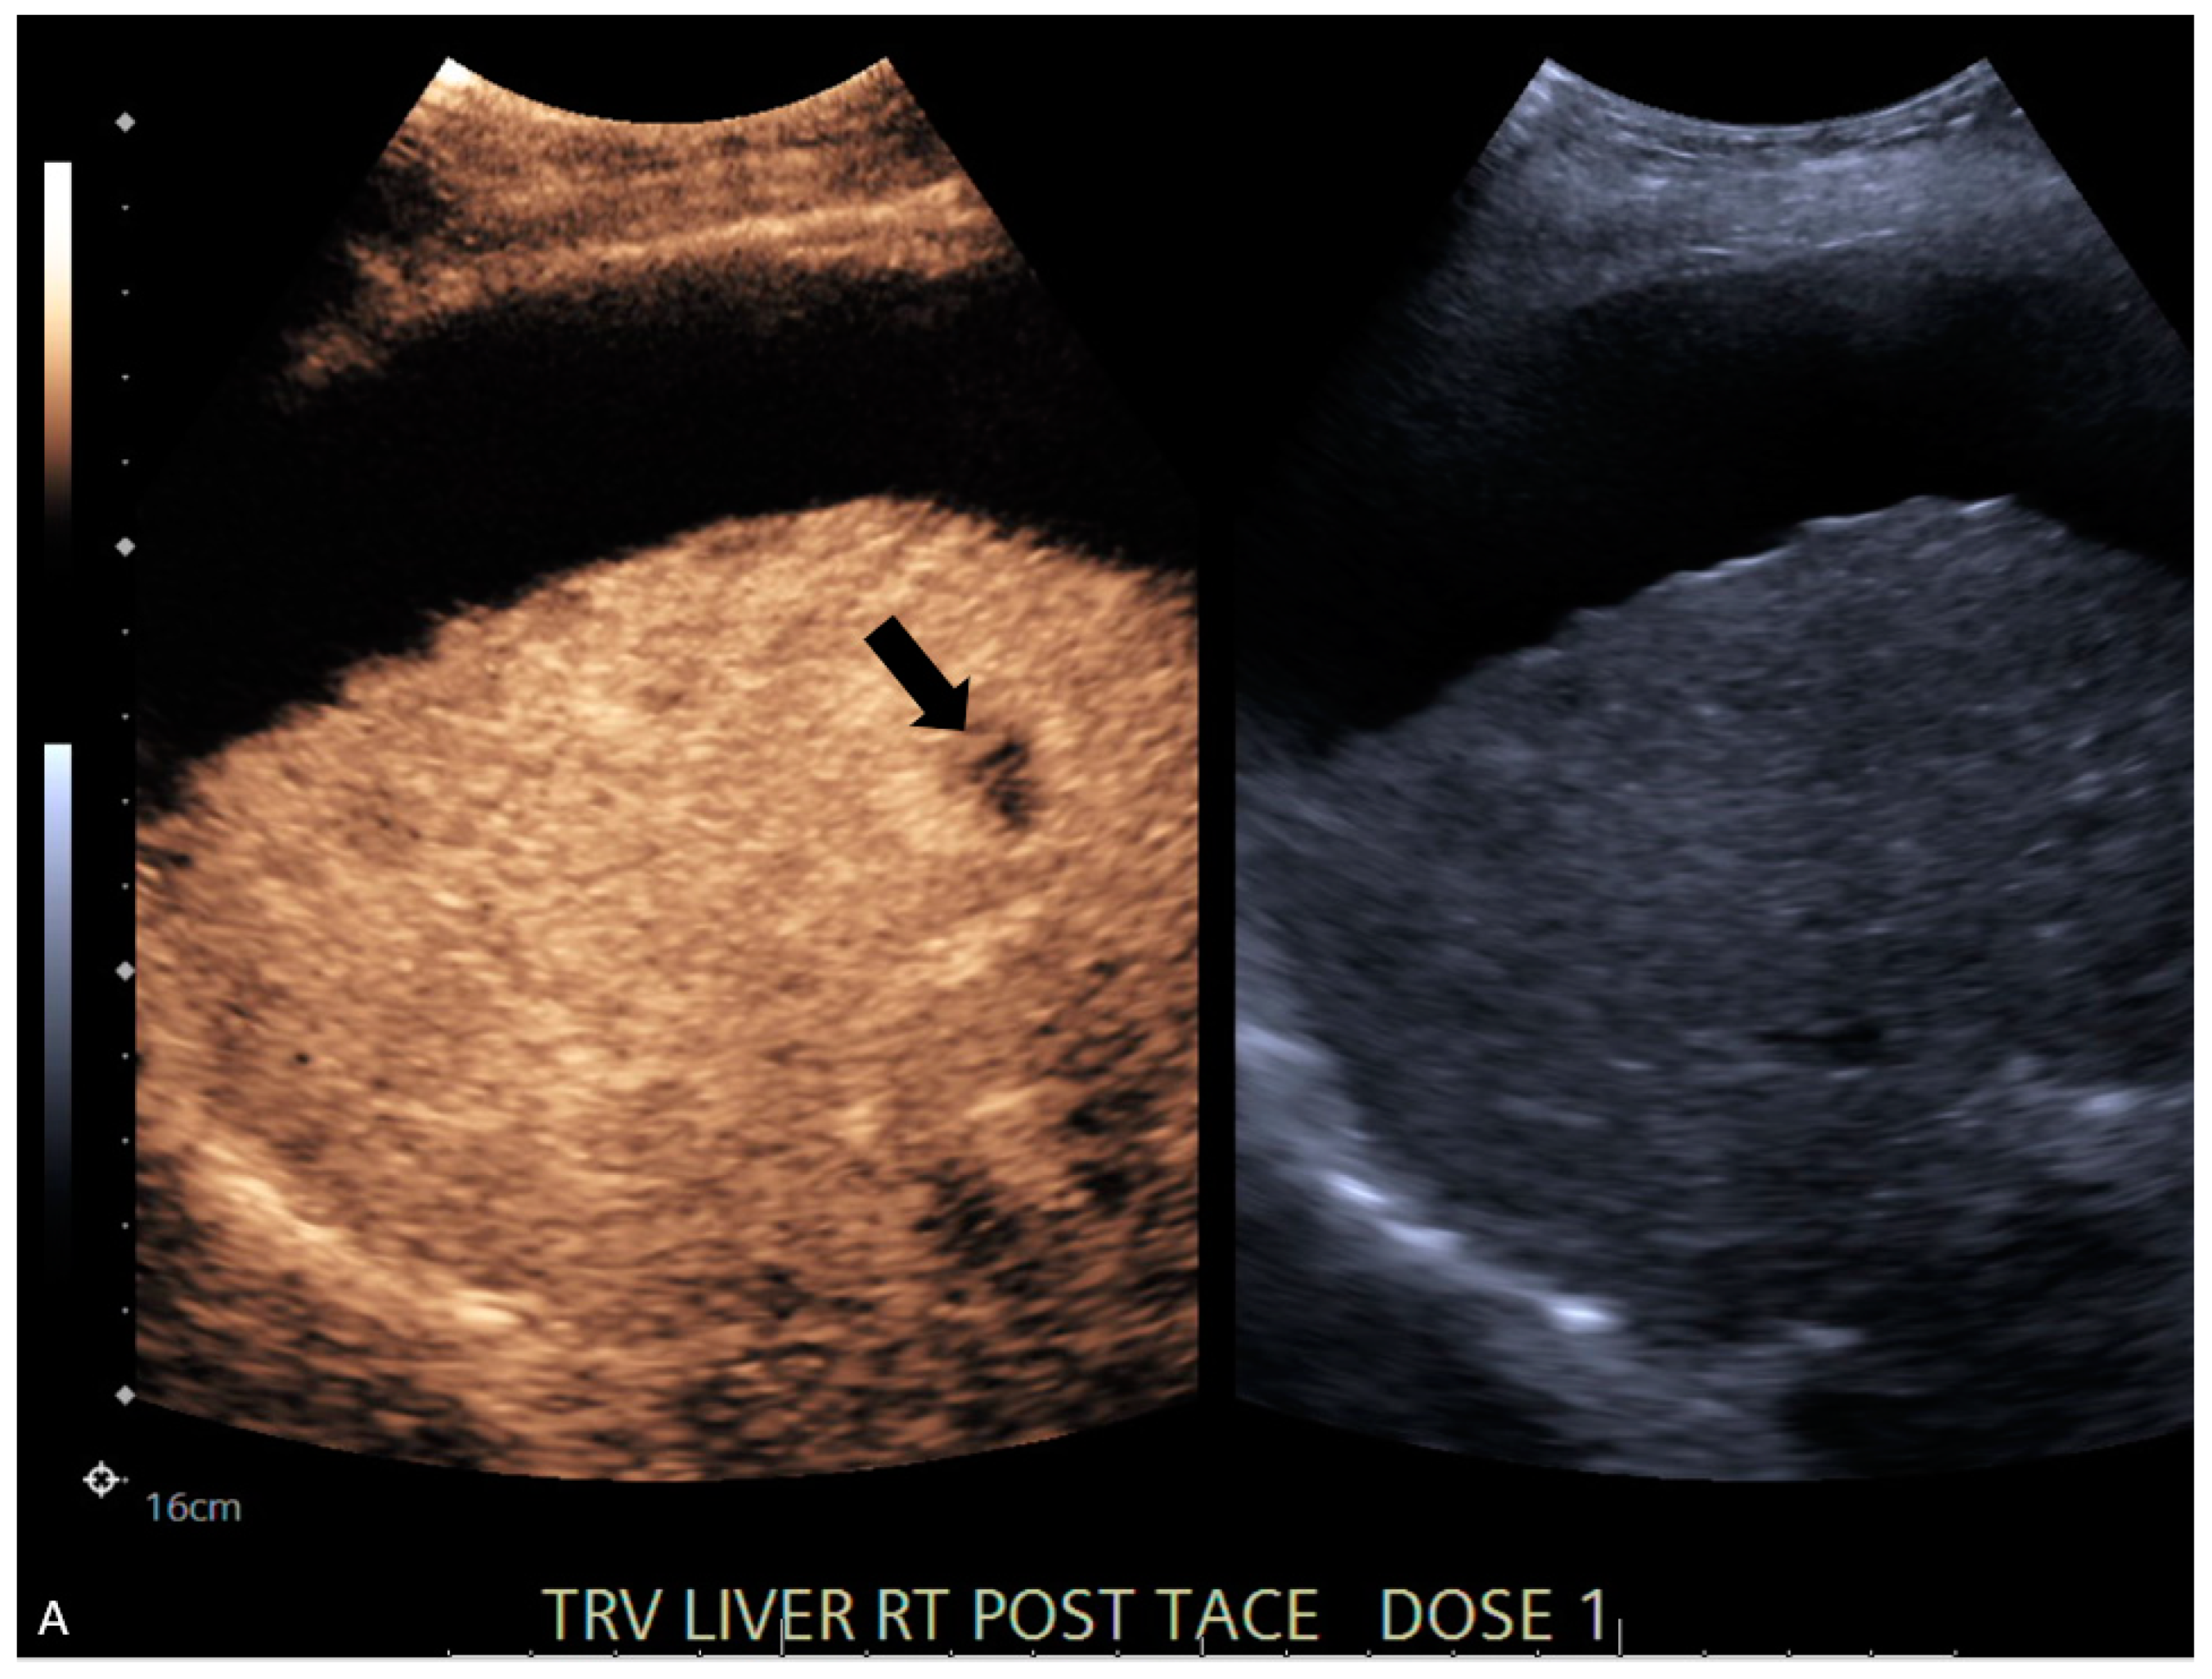

| 6 | CEUS | Target | LR-viable | CT missed subtle disease at the periphery of the treated HCC (Figure 2) |